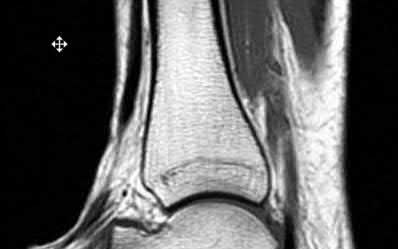

A 25-year-old male sustains an ankle fracture dislocation and undergoes open reduction and internal fixation. He returns to clinic five months following surgery complaining of continued ankle pain and instability with weight bearing. His immediate post-operative AP radiograph is seen in Figure A. Which of the following could have prevented this patient from developing persistent pain?

The patient presents with continued ankle pain and instability following open reduction and internal fixation. The radiograph in figure A demonstrates inadequate restoration of fibular length, likely leading to continued tibiotalar instability.